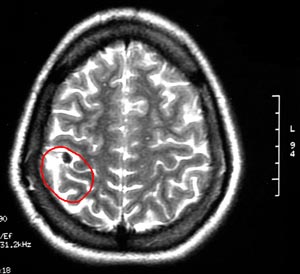

3b) Neurocisticercose

Figura 58 - Ressonância nuclear magnética pré-operatória.